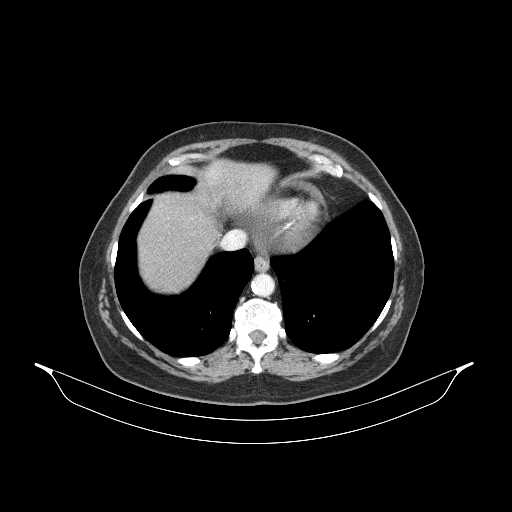

Generated VENOUS CT scan (A→B translation)

Full window (WL 1023.5, WW 4095 β†’ Low βˆ’1024, High +3071)

Lung window (WL -600, WW 1500 β†’ Low βˆ’1350, High +150)

Mediastinum window (WL 40, WW 400 β†’ Low βˆ’160, High +240)